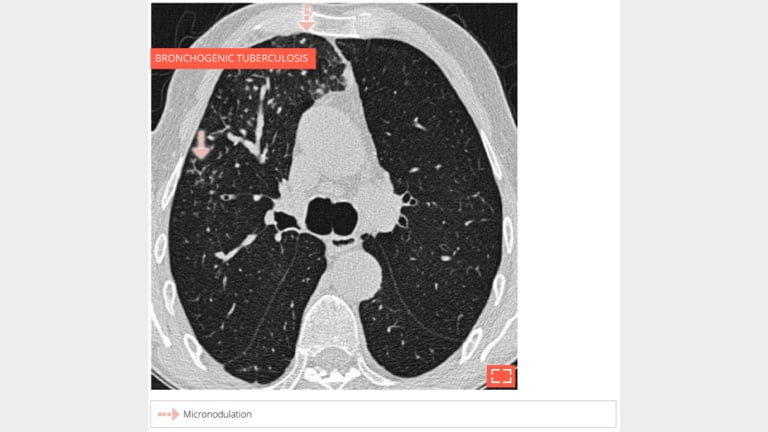

2. Micronodulation

Micronodulation

Centrilobular and perilymphatic micronodulation.